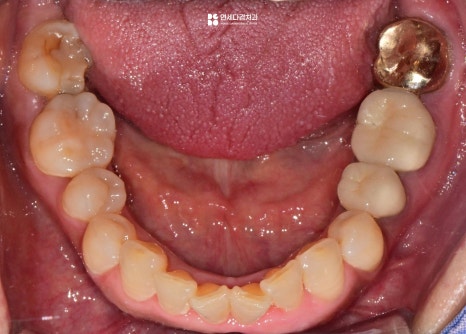

이렇게 눈으로 살펴봤을 때는

특별한 이상은 없는 것처럼 보이지만,

실제로는 통증을 느끼는 경우가 있습니다.

이는 구강 안에 육안으로 확인하기 어려운

사각지대가 존재하기 때문입니다.

이 사각지대 중 하나가 인접면입니다.

치아의 옆면은 음식이 자주 끼는 곳이지만,

이물질을 제거하기 어렵고 확인도 어렵기 때문에

우식이 자주 발생하는 부위입니다.